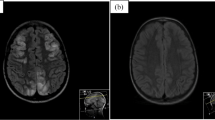

Neuroimaging data were classified based on lesion location patterns and severity. Lesion location patterns were categorized based on cerebral edema distribution (Fig. 1) as posterior, anterior, diffuse, brainstem-cerebellum, or basal ganglia [12]. Lesion severity was categorized as mild, moderate, or severe according to the vasogenic edema extent, the involvement of deep structures (cerebellum, brainstem, or basal ganglia), and the presence of parenchymal hemorrhage [13].

The following neuroimaging techniques were used for the evaluation of disease onset in the 52 patients: MRI (n = 24); CT followed by MRI (n = 22); CT (n = 6). A CT with a contrast agent was obtained in four cases. An invasive digital subtraction angiography study was performed in two cases [17, 27]. The following magnetic resonance imaging sequences were used in the 46 patients: T2WI and/or FLAIR, n = 46; DWI with ADC, n = 20; TOF, n = 3; T1 C + , n = 7. A posterior pattern of distribution was detected in 28 cases, a diffuse pattern in 23 cases, and a brainstem-cerebellum-predominant pattern in the remaining case [14]. No patient was found to have an anterior or a basal ganglia pattern. The neuroimaging severity score was mild in about 95% of cases.

The term PRES was adopted 25 years ago [1] because neuroimaging studies detected a brain edema situated in the subcortical white matter of the occipital region. This edema pattern was noted in slightly more than half of our cases. In this study, however, we observed a diffuse edema in more than 40% of cases, as reported in the recent literature [2, 12, 13]. It has been therefore suggested to abandon the word “posterior” and use instead terms such as reversible leukoencephalopathy syndrome or acute brain capillary leak syndrome [2]. Interestingly, demographics, the clinical features, and the severity of arterial hypertension and kidney disease did not differ between patients with posterior and diffuse brain edema. Intracranial hemorrhage and ischemia may occur in a minority of patients with PRES, as confirmed by the present analysis [2]. Remarkably, two of the three patients with the aforementioned complications of PRES were affected by sickle cell anemia. Since PRES is being increasingly recognized in sickle cell anemia [63], we tentatively speculate that both acute glomerulonephritis and sickle cell anemia might have contributed to the development of PRES.

The present data do not allow us to suggest the management of PRES in acute postinfectious glomerulonephritis. However, it is assumed but not proven that early recognition and treatment are of paramount importance because PRES is usually reversible with appropriate management [2, 59, 60, 64]. Neuroimaging is essential to the diagnosis. While a brain CT scan is sometimes the first study performed, a brain magnetic resonance imaging with an imaging protocol tailored to PRES is the critical imaging method [65].